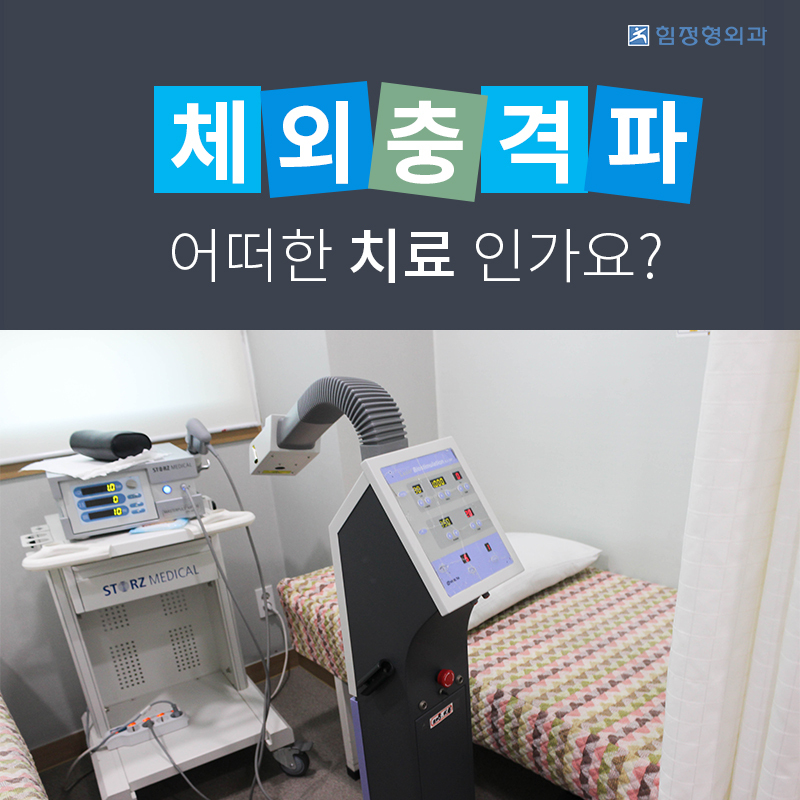

물리치료,도수치료, 주사치료, 체외 충격파와 고출력 레이저 시술을 통해

호계동관절병원 체외충격파는 병변 부위에 충격파를 전달하고

충격파로 인해 혈관을 빠르게 활성화시켜주면서

뼈와 조직을 치료하는 방식으로

이는 병변 부위를 재활성화 시켜줌으로써

통증을 줄일수 있습니다.